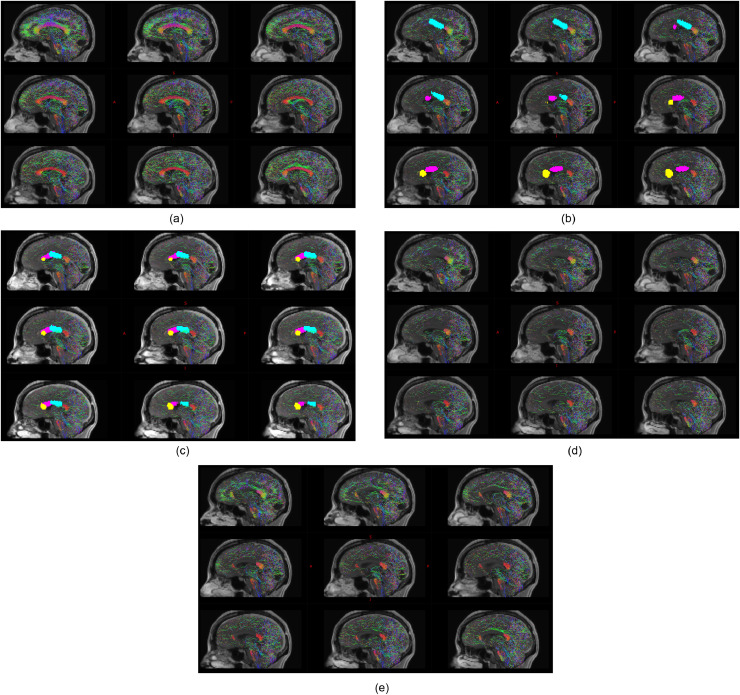

Based on the simulated ablation cavities, 4 out of 10 patients and 2 out of 10 patients following expert 1 and 2 manual trajectory planning, respectively, had residual hemispheric connectivity through the anterior two-thirds of the corpus callosum compared to 1 out of 10 following computer-assisted planning. In all cases, the residual interhemispheric connectivity was at the anterior-most aspect of the genu of the corpus callosum and related to cortical vasculature restricting the non-dominant frontal lobe trajectory from targeting the rostrum. The mean volume of the unablated anterior two-thirds corpus callosum was 0.69 cm3 compared to an intentionally unablated splenium volume of 3.5 cm3 and total corpus callosum volume of 15.4 cm3 (see Fig. 5).

Fig. 5.

Legend: Example of residual interhemispheric connectivity identified from probabilistic tractography shown on median and paramedian sagittal planes. Streamline directionality encoded as red: right-left, blue: superior-inferior and green: anterior-posterior. A) Baseline interhemispheric probabilistic tractography in a single subject. B) Corresponding computer-assisted and C) manual plan derived estimated ablation volumes with the non-dominant frontal trajectory to the rostrum of corpus callosum shown in yellow, the non-dominant parietal trajectory to the genu of corpus callosum shown in magenta and the dominant frontal trajectory to the posterior body of the corpus callosum shown in cyan. D) Simulated effect of computer-assisted and E) manual plan estimated ablation cavities on structural interhemispheric connectivity, revealing residual connectivity at the genu of the corpus callosum associated with the manual plan compared to the computer-assisted plan (shown as red streamlines at the genu of the corpus callosum).